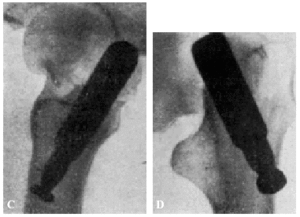

Muchos fracasos de Böhler se deben a haber cargado precozmente la extremidad. La figura 15, A y B8, corresponde a un fracturado operado por Böhler. El clavo está bien colocado en las dos proyecciones, aunque es poco profundo y ligeramente ventral en lugar de dorsal. A los dos meses, cuando el enfermo andaba perfectamente bien, nota el enfermo bruscamente dolores y se comprueba a la exploración radiográfica que el clavo se había salido de la cabeza del fémur (fig. 15, C y D). Dice Böhler, referente a este caso: «Este desprendimiento no habría ocurrido si el clavo se hubiera colocado algo más caudal y más dorsal respecto a la línea media del cuello y de la cabeza y, a la vez, hubiese penetrado lo suficiente en ésta». Y añadimos nosotros: a pesar de que la situación del clavo no era idealmente perfecta en este caso, la culpa del fracaso reside fundamentalmente en la carga precoz del miembro fracturado. Si observamos la figura 16, A y B (observación núm. 23), aunque en proyección anteroposterior, la situación del clavo puede considerarse perfecta; en proyección lateral, está en situación mucho más ventral que la observación anterior de Böhler, y sin embargo la enferma, operada en mayo de 1941, anda en la actualidad, a pesar de sus setenta y ocho años, sin la ayuda de ningún bastón y sin presentar ninguna molestia (fig. 16 C). La situación del clavo en este caso es muy semejante a la de la enferma citada anteriormente, que falleció al extraerle el clavo intolerante (supuración de la herida, sin síntomas generales de infección) (fig. 17 A y B; obs. núm. 18), por lo que todo hace suponer que, en caso de no haberse presentado el desenlace fatal, el resultado funcional hubiera sido bueno.

Figura 15. A: comprobación roentgenológica después de colocar el clavo e impactar los fragmentos. La diástasis entre éstos ha desaparecido. El clavo está en el centro del cuello y de la cabeza, pero no lo suficiente profundo, puesto que su punto dista 13 mm. de la superficie de la cabeza, en vez de 3 a 6 mm. B: en la proyección lateral, el clavo está colocado algo hacia delante, es decir, demasiado ventral, en la cabeza del fémur. (De Böhler Jeschke.)

Figura 15. C y D: al principio andaba perfectamente, pero de pronto se le presentaron dolores, y en la roentgenografía se vio que el clavo se había salido de la cabeza del fémur y los fragmentos habían vuelto a desviarse a la posición que tenían antes de la reducción. Este desprendimiento no habría ocurrido si el clavo se hubiera colocado algo más caudal y más dorsal respecto a la línea media del cuello y de la cabeza, y, a la vez, hubiese penetrado lo suficiente en ésta. (De BöhlerJeschke.)